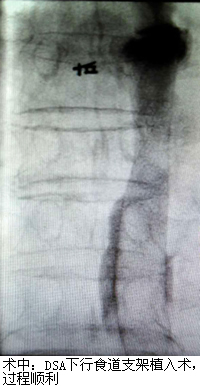

郑老伯今年已81岁高龄,因“进行性吞咽困难1月余”就诊当地医院,诊断结果为晚期食管癌。由于年纪大不宜手术,郑老伯一年内行多次放化疗后仍出现食管肿物进行性增大,原来吃面食现在只能喝水,甚是痛苦。经打听,他们了解到福建医科大学附属第一医院介入科通过一种无创的食道支架植入术可以姑息性治疗晚期食管癌,遂转诊我院。在充分了解病情及完善相关检查后,我院介入科治疗团队为郑老伯进行了这种无创手术,手术很顺利,疗效显著。术后第二天医生告诉老伯可以继续吃面食了,郑老伯非常开心,其家属也相当满意,十分感谢我院陈一平、陈仲武两位专家及其团队。

陈一平、陈仲武副主任医师介绍说,食管癌的最大问题是因食道阻塞而患者无法进食,常规上会以肠或胃造瘘的方式解决患者营养或者排便的问题。但胃造瘘仍无法让患者经口进食,而食道支架,可用以撑开肿瘤阻塞的食道,满足患者经口进食的口欲,使患者的营养得到保障,此外,该手术具有疼痛轻、并发症少等优点,对患者也是巨大的心理安慰。食道支架植入术是晚期食管癌患者实现食道再通的一种有效治疗手段。